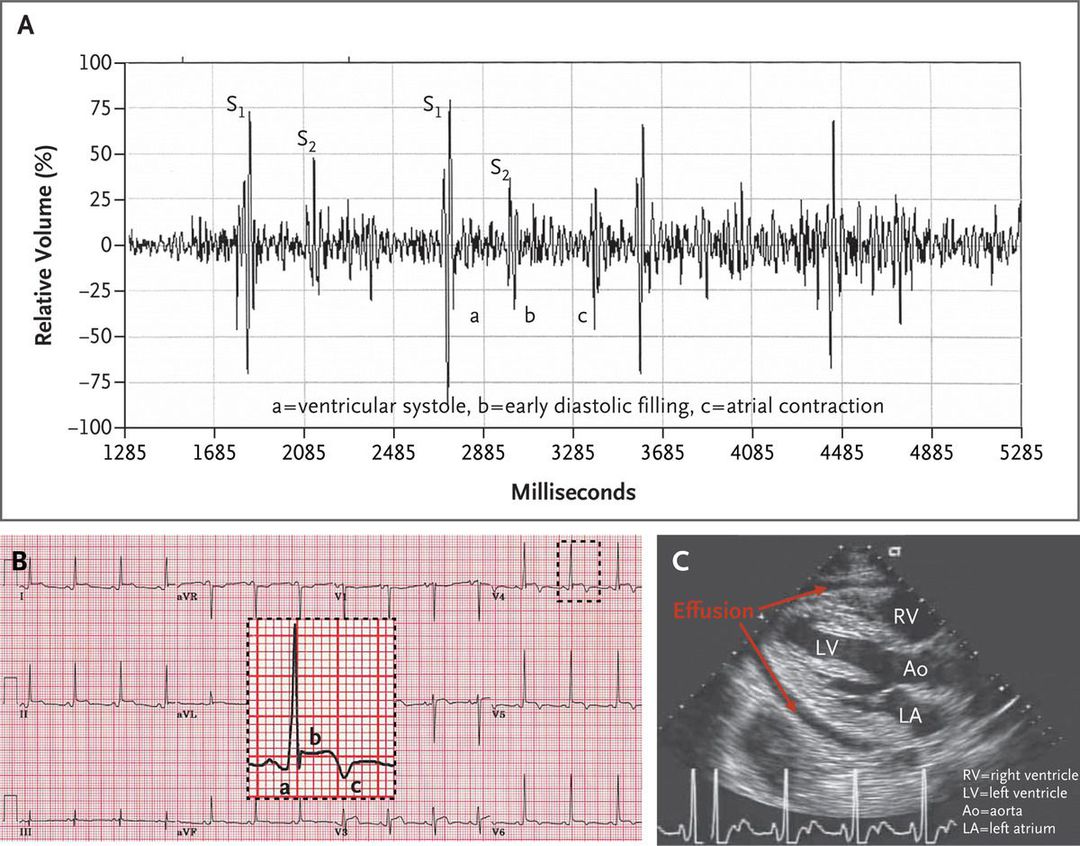

A 33-year-old soldier presented with a 5-day history of unremitting substernal chest pain that radiated to his shoulders. The pain was worse when he was lying down and improved when he leaned forward. He reported having no dyspnea. He had no chest-wall tenderness and had not undergone any recent trauma. Laboratory analysis revealed an elevation in the white-cell count, erythrocyte sedimentation rate, and fibrin D-dimer level. In the emergency department, his cardiac-enzyme levels were found to be normal, as were results on computed tomography for pulmonary embolism. The next day, a three-component friction rub was heard during auscultation An electrocardiogram showed PR-segment depression (Panel B, label a) with elevation in lead aVR, diffuse ST-segment elevation (Panel B, label b) with depression in lead aVR, and T-wave inversion in the precordial leads (Panel B, label c). A moderate-sized and hemodynamically insignificant pericardial effusion was seen on echocardiography (Panel C). No cause of the acute pericarditis was found. The patient's condition improved with the administration of ibuprofen and colchicine.